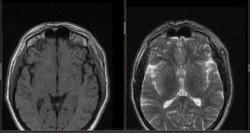

- https://radiomed.ru/sites/default/files/styles/case_slider_image/public/user/16807/2_41.jpg?itok=Phr_eCUu

- https://radiomed.ru/sites/default/files/styles/case_slider_image/public/user/16807/8_3.jpg?itok=_0vgWjN6